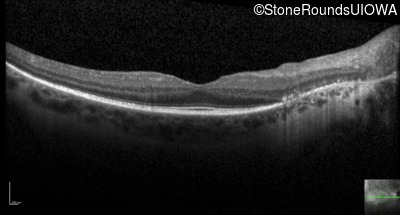

Optical Coherence Tomography - Left - 20/32 -1

Exemplar / OCT Stack

OCT Stack